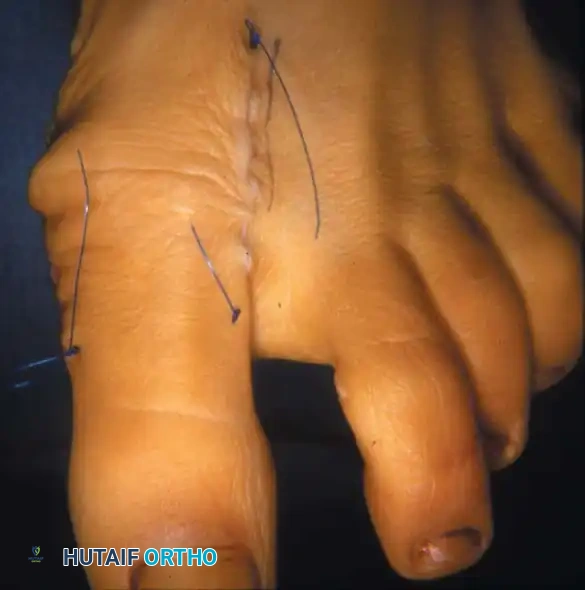

Fig. 78-12 Hallux valgus treated by modifi ed McBride procedure. A, Preoperative deformity in 30-year-old patient. B, Correction obtained at surgery. C, Preoperative and postoperative radiographs (note fi bular sesamoid was not removed). More deformity can be corrected by fi bular sesamoidectomy, but overcorrection (hallux varus) is risk. If fi bular sesamoid is excised, medial capsule should be closed while holding hallux in 5 to 10 degrees valgus and kept in that position until capsular healing.